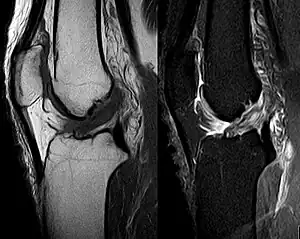

Medical imaging

Though clinical examination in experienced hands can be accurate, the diagnosis is usually confirmed by magnetic resonance imaging, which provides images of the soft tissues like ligaments and cartilage around the knee.[1] It may also permit visualization of other structures which may have been coincidentally involved, such as the menisci or collateral ligaments.[33] An x-ray may be performed in addition to evaluate whether one of the bones in the knee joint was broken during the injury.[9]

MRI is perhaps the most used technique for diagnosing the state of the ACL, but it is not always the most reliable technique as the ACL can be obscured by blood that fills the joint after an injury.[34]

MRI is particularly useful in cases of partial tear of the ACL. The anteromedial band is most commonly injured compared to the posterolateral band.[35]